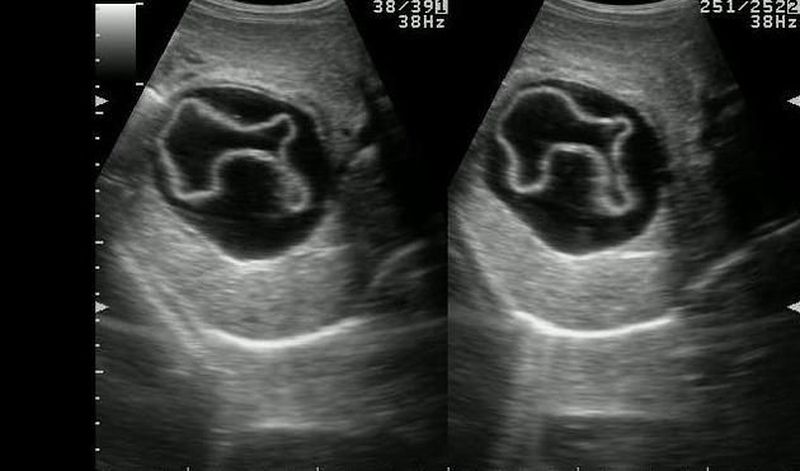

Radiology: Water Lily Sign

It is the USG appearance of hydatid cyst. The inner layer of cyst may separate from outer layer & appears as a Serpentine structure inside of cyst.